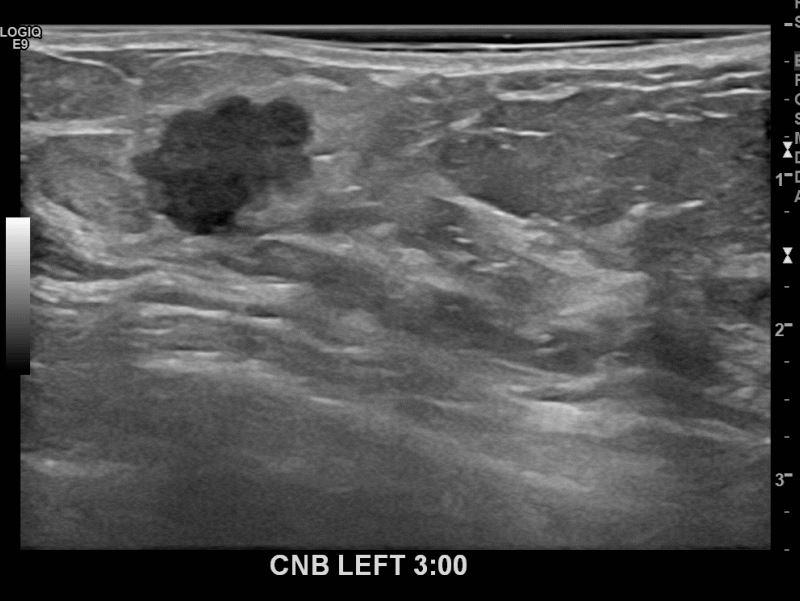

아산유외과 개원후 662번째 유방암진단

상기환자 외부검사상 이상소견으로 내원하신 70대여성으로 좌측에 의심스러운혹 조직검사시행해 유방암 진단되었습니다.